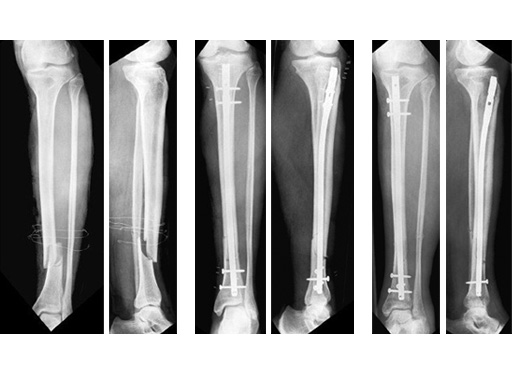

Type III open distal tibial fracture with beginning compartment syndrom following a traffic accident.

60-year-old man with a type II open 42-A2 fracture following a working accident.